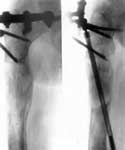

2.Удаление нежизнеспособных тканей нижней трети бедра с одновременным удлинением бедра аппаратом Илизарова.